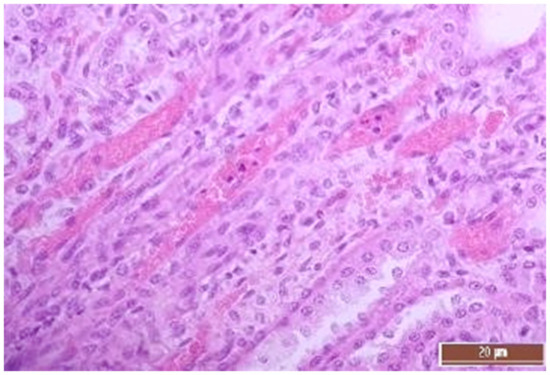

3.2. Pathology of the Liver